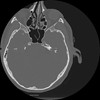

7 HUESO,,Vol,0.5,HUESO,,